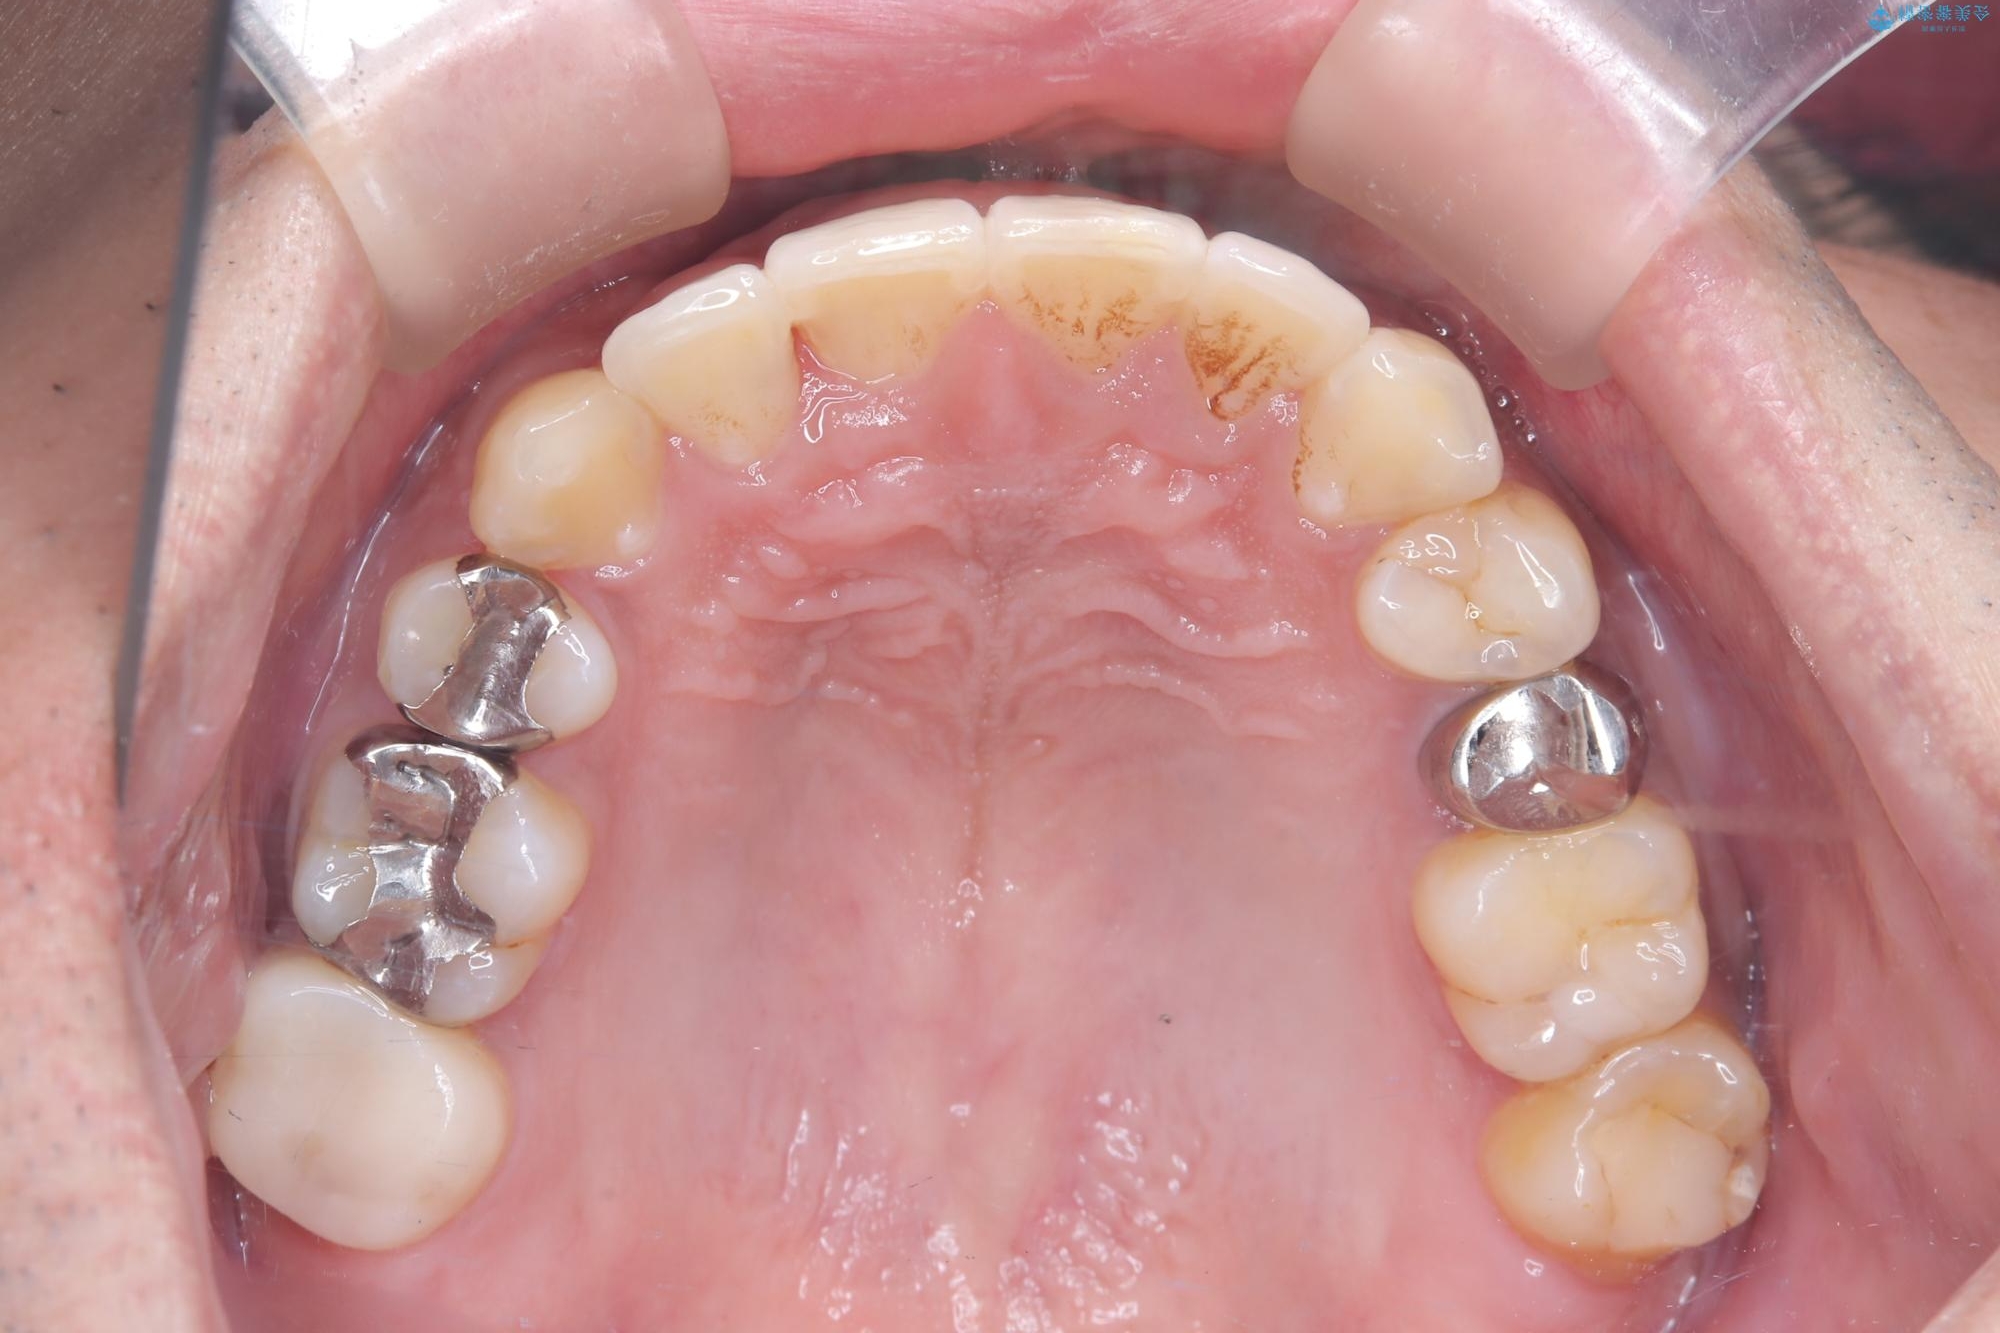

- 主訴:右上の八重歯と、下の歯の凸凹を治したい

上顎右側第一小臼歯と下顎右側第一小臼歯を抜歯しワイヤー矯正を行いました。

右側2級、左側1関係だったため、右側上下第一小臼歯を抜歯し、ワイヤー矯正を行いました。